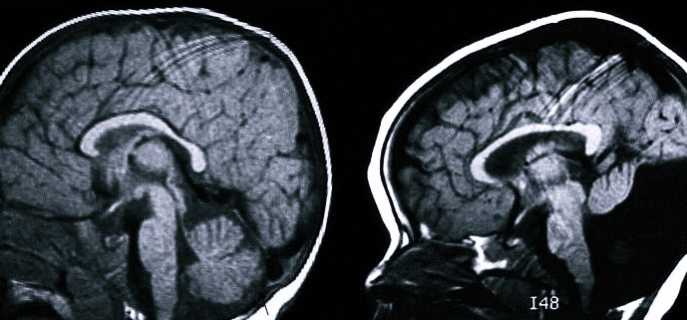

- Делается КТ и МРТ. Во время процедуры определяют факт разрастания задней ямки черепной коробки, увеличения в объемах 4-го желудочка, скопления жидкости в мозговых пустотах, недоразвитие мозжечка.